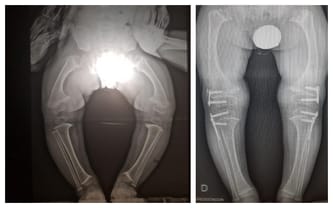

To niesamowite, jaką różnicę możemy zobaczyć po operacji doktora Paleya. Naprawdę chcielibyśmy Wam jeszcze raz podziękować z całego serca za Wasze wsparcie i to finansowe i to duchowe. Dzięki Wam Jurek już się nie przewraca. To porównanie zdjęć RTG mówi zresztą samo za siebie.